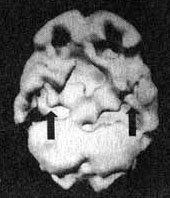

Мозг Эллен — последствия инсульта ![]() Трехмерное изображение поверхности мозга, вид слева. Обратите внимание на обширную «дыру», сформировавшуюся в результате инсульта в левой лобной доле 2. SPECT позволяет дать точную оценку состояния пациента, позволяющую предотвратить, заболевание в будущем. Нэнси, 59 лет, страдала от тяжелой депрессии, не поддававшейся лечению. Поступила в психиатрическую лечебницу, где ей было проведено исследование SРЕСТ. Каково же было мое удивление, когда оказалось, что в прошлом, при полном отсутствии соответствующих симптомов, она перенесла два обширных инсульта. Таким образом, стало понятно, что вызвало эту депрессию, не поддававшуюся обычному лечению. У 60 % пациентов, перенесших кровоизлияние во фронтальных долях, через год развивается тяжелая депрессия. Получив результаты SPECT, я немедленно проконсультировался с неврологом, который постарался определить причины инсультов, к которым нередко приводят, скажем, бляшки в сонных артериях или сердечная аритмия. Он пришел к выводу, что причиной инсультов у Нэнси стали тромбы, и назначил ей препараты, снижающие вязкость крови, чтобы предотвратить развитие новых инсультов. Мозг Нэнси — последствия двух инсультов ![]() Трехмерное изображение поверхности, вид сверху ![]() Трехмерное изображение поверхности, вид справа 3. С помощью SPECT можно получить информацию, помогающую врачу добиться понимания и сострадания к пациенту у членов его семьи. Фрэнк — состоятельный, хорошо образованный человек. Вскоре после того как ему исполнилось 70 лет, он стал забывчивым. Сначала он забывал мелочи, но со временем провалы в памяти стали прогрессировать, и он начал забывать значимые факты собственной биографии: где он живет, как зовут его жену и даже как зовут его самого. Жена и дети были не в состоянии понять, чем вызваны такие перемены, а его рассеянность и забывчивость их нередко раздражали. Результаты SPECT показали, что у Фрэнка на всей поверхности мозга отмечается резкое снижение активности, и особенно во фронтальных, париетальных и височных долях. Это была классическая картина синдрома Альцгеймера. Показав семье снимки и объяснив, что забывчивость Фрэнка имеет четкую физиологическую природу, я помог им осознать, что он не специально раздражает их, а серьезно болен. Впоследствии, вместо того чтобы упрекать его за забывчивость, близкие Фрэнка стали поддерживать его и разработали схемы, позволившие эффективнее бороться с трудностями, возникающими у всякого, кто вынужден жить рядом с человеком, страдающим болезнью Альцгеймера. Мозг Фрэнка — болезнь Альцгеймера ![]() Трехмерное изображение поверхности, вид сверху ![]() Трехмерное изображение нижней поверхности Обратите внимание на выраженное общее снижение активности, особенно в париетальных долях (см. стрелки, рис. слева) и в височных долях (см. стрелки, рис. справа). 4. SPECT позволяет проводить дифференциальную диагностику состояний со сходной симптоматикой. Я познакомился с Маргарет, когда ей было 68. Выглядела она неухоженно и неопрятно. Маргарет жила одна, и ее близких это очень беспокоило, так как у нее появились симптомы тяжелой деменции. После того как она чуть не сожгла дом, оставив включенной плиту, ее поместили в психиатрическую клинику, где в то время работал я. Из общения с ее близкими обнаружилось, что Маргарет часто забывала, как зовут ее собственных детей, и нередко, ведя машину, сбивалась с дороги и оказывалась в незнакомом месте. Водительские навыки ухудшились настолько, что после четырех небольших ДТП всёго за шесть месяцев у нее отобрали права. К тому времени, когда я встретился с ее близкими, многих из них эта ситуация уже утомила, и они были готовы сдать Маргарет в специализированный приют. Другие были против такого решения и хотели бы сначала обследовать ее в условиях стационара. На первый взгляд казалось, что Маргарет страдает болезнью Альцгеймера. Однако по результатам SPECT обнаружилось, что активность мозга в париетальных и височных долях не нарушена. Если бы у нее был синдром Альцгеймера, кровоток в этих областях должен был бы быть снижен. Вместо этого единственной патологией, которую нам удалось обнаружить на снимках SPECT, стала зона повышенной активности в глубокой лимбической области в центре мозга. Такая картина часто наблюдается у пациентов, страдающих депрессией. Из-за схожей симптоматики у больных старшего возраста нередко бывает трудно дифференцировать депрессию и болезнь Альцгеймера. Тем не менее при псевдодеменции (депрессии, которая выглядит как слабоумие) человек может выглядеть слабоумным, на самом деле таковым не являясь. Это чрезвычайно важный момент, так как, диагностировав болезнь Альцгеймера, мы даем близким ряд специальных рекомендаций и назначаем пациенту некоторые медикаментозные средства. Между тем, диагностируя депрессию, мы проводим агрессивную медикаментозную терапию антидепрессантами в сочетании с психотерапией. Результаты обследования Маргарет убедили меня в том, что ей следует назначить антидепрессант Wellbutrin (бупропион). Всего три недели спустя она уже была разговорчивой, ухоженной и охотно общалась с другими пациентами. Через месяц после госпитализации ее выписали домой. Перед выпиской она попросила меня написать письмо в автоинспекцию с просьбой вернуть ей водительские права. Поскольку мы с ней ездим по одному и тому же шоссе, я заколебался. Я сказал ей, что, если улучшение будет стойким и сохранится на протяжении по меньшей мере полугода, а сама она станет придерживаться рекомендаций врача и принимать все лекарства, я напишу письмо в автоинспекцию. Через полгода она оставалась в хорошей форме. Я сделал повторный SPECT — результаты показали полную норму. Тогда я обратился в автоинспекцию, и ей вернули права. Мозг Маргарет — псевдодеменция ![]() Трехмерное изображение снизу — активный мозг, до лечения. ![]() Трехмерное изображение снизу активный мозг, после лечения. |